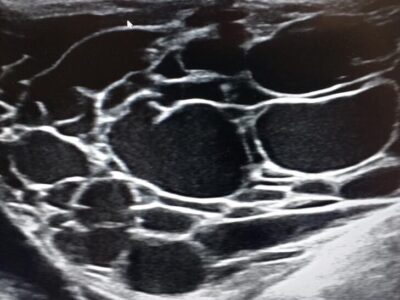

Gallbldder mucocele - kiwi fruit

Gallbldder mucocele - kiwi fruit -

Gynecomastia - ultrasound of the mammary gland

Gynecomastia - ultrasound of the mammary gland -